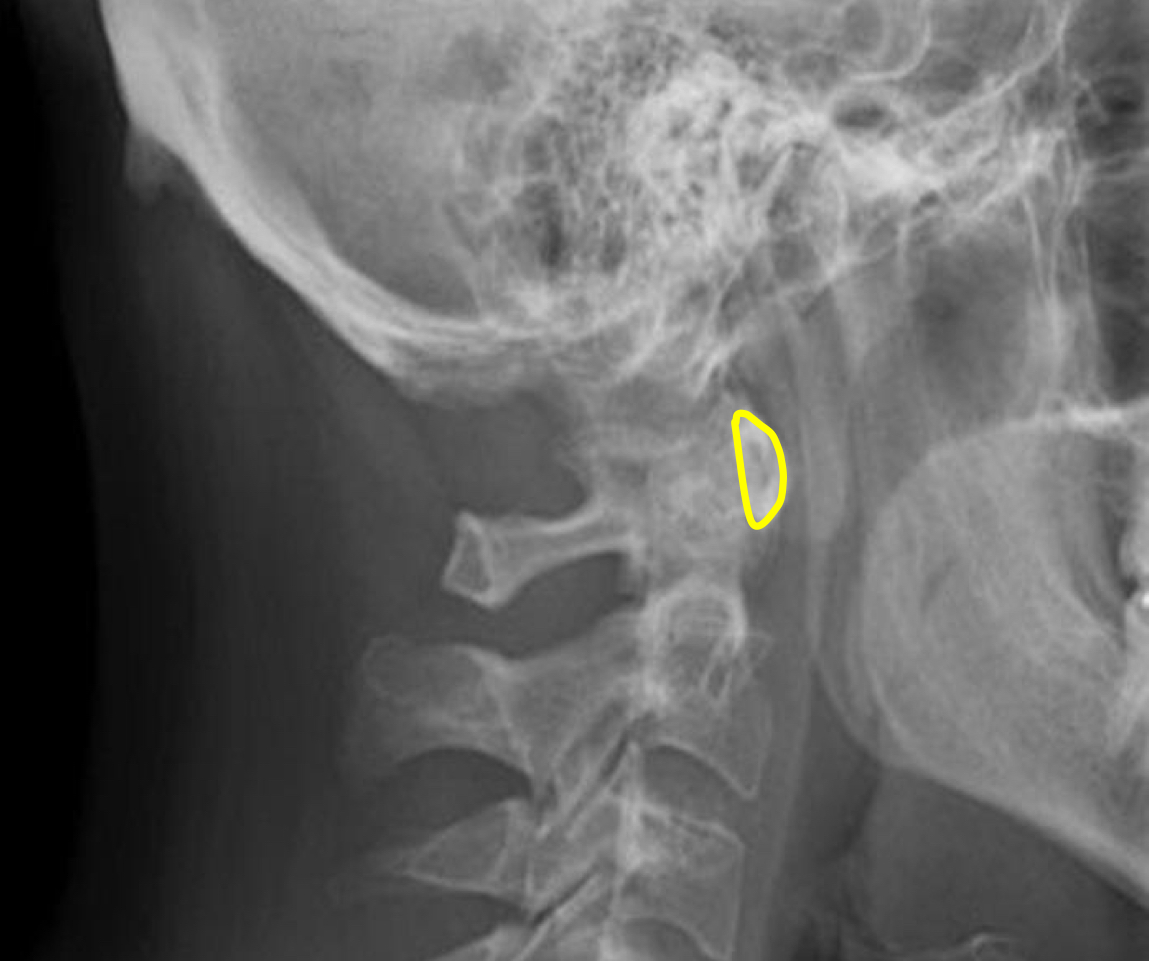

What view is this?

Lateral Cervical

What is this?

Vertebral Bodies

What is this?

Superior and Inferior Endplate Tips

What is this?

Disc space

What is this?

Mandible

What is this?

Hyoid bone

What is this?

Mitchel Marker

What is this?

Occipital Condyle

What is this?

C1 Anterior Tubercle

What is this?

C1 Posterior Arch

What is this?

Odontoid Process

What is this?

Atlanto-Dental Interspace